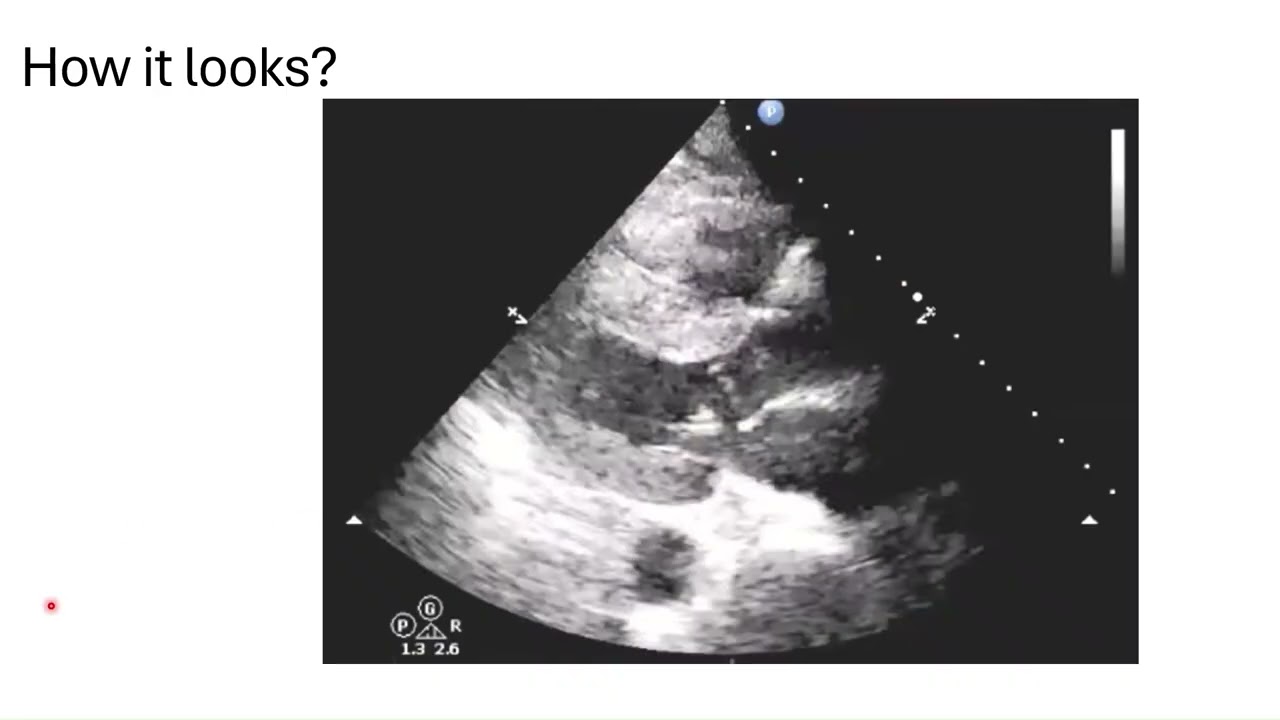

Dynamic LVOT Obstruction on Echo

Pathophysiology and clinical implications of Dynamic LVOT Obstruction!